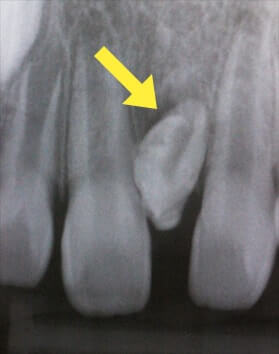

萌出異常(永久歯が乳歯に引っかかっている)